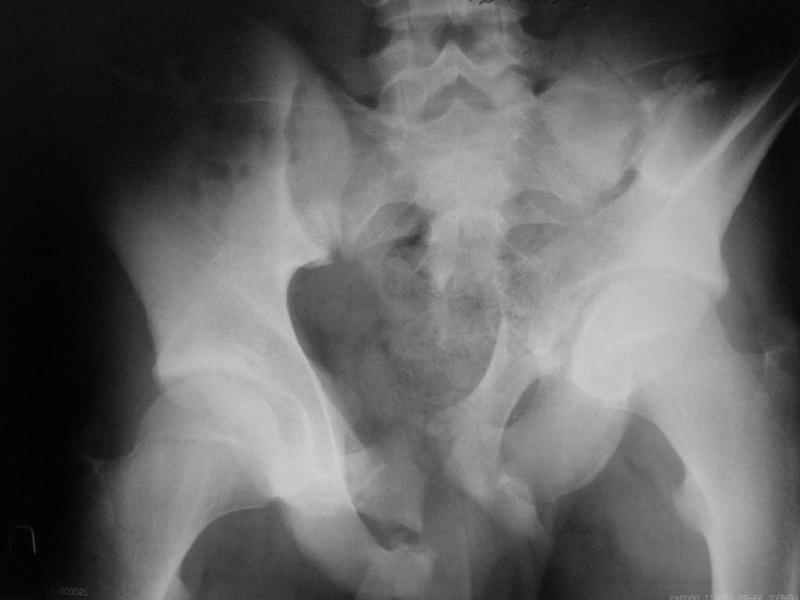

Коллеги, помогите определиться с тактикой лечения пациента. Ув. коллеги, к нам поступил молодой человек 17 лет. Травма в июле 2005- ДТП, т.е. 3 мес назад. Лечился консервативно в "гамаке" 1,5 мес., затем ходьба с костылями без опоры на левую нижнюю конечность, начал на нее опираться 1 нед назад. В настоящее время имеется укорочение порядка 4-5 см, выраженная хромота, передвигается с одним костылем. Кроме того беспокоят боли в пояснично-крестцовой области при ходьбе, неудобство при сидении, невозможность лежать на спине "на жестком", а также на левом боку (субъект худощавый, боль в области крыла) хромота, длительное пребывание на ногах невозможно. На функциональных снимках большой подвижности нет (не привожу из-за плохого качества). Учитывя наличие участков сращений, помогите опредилиться с тактикой. Наш план пока такой: 1. выполнить остеотомии в участках сращений 2.постепенно аппаратом низвести смещенную половину таза. 3.выполнить внутренний остеосинтез передних и задних отделов. Будем признательны за ваш взгляд на тактику леченияэтого больного, а так же на такие проблемы как: места остеотомий, возможные варианты компоновки аппарата, выбор имплантатов для последующего вмешательства.